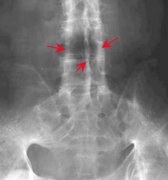

强直性脊柱炎检查

• 强直性脊柱炎检查常用三种方法